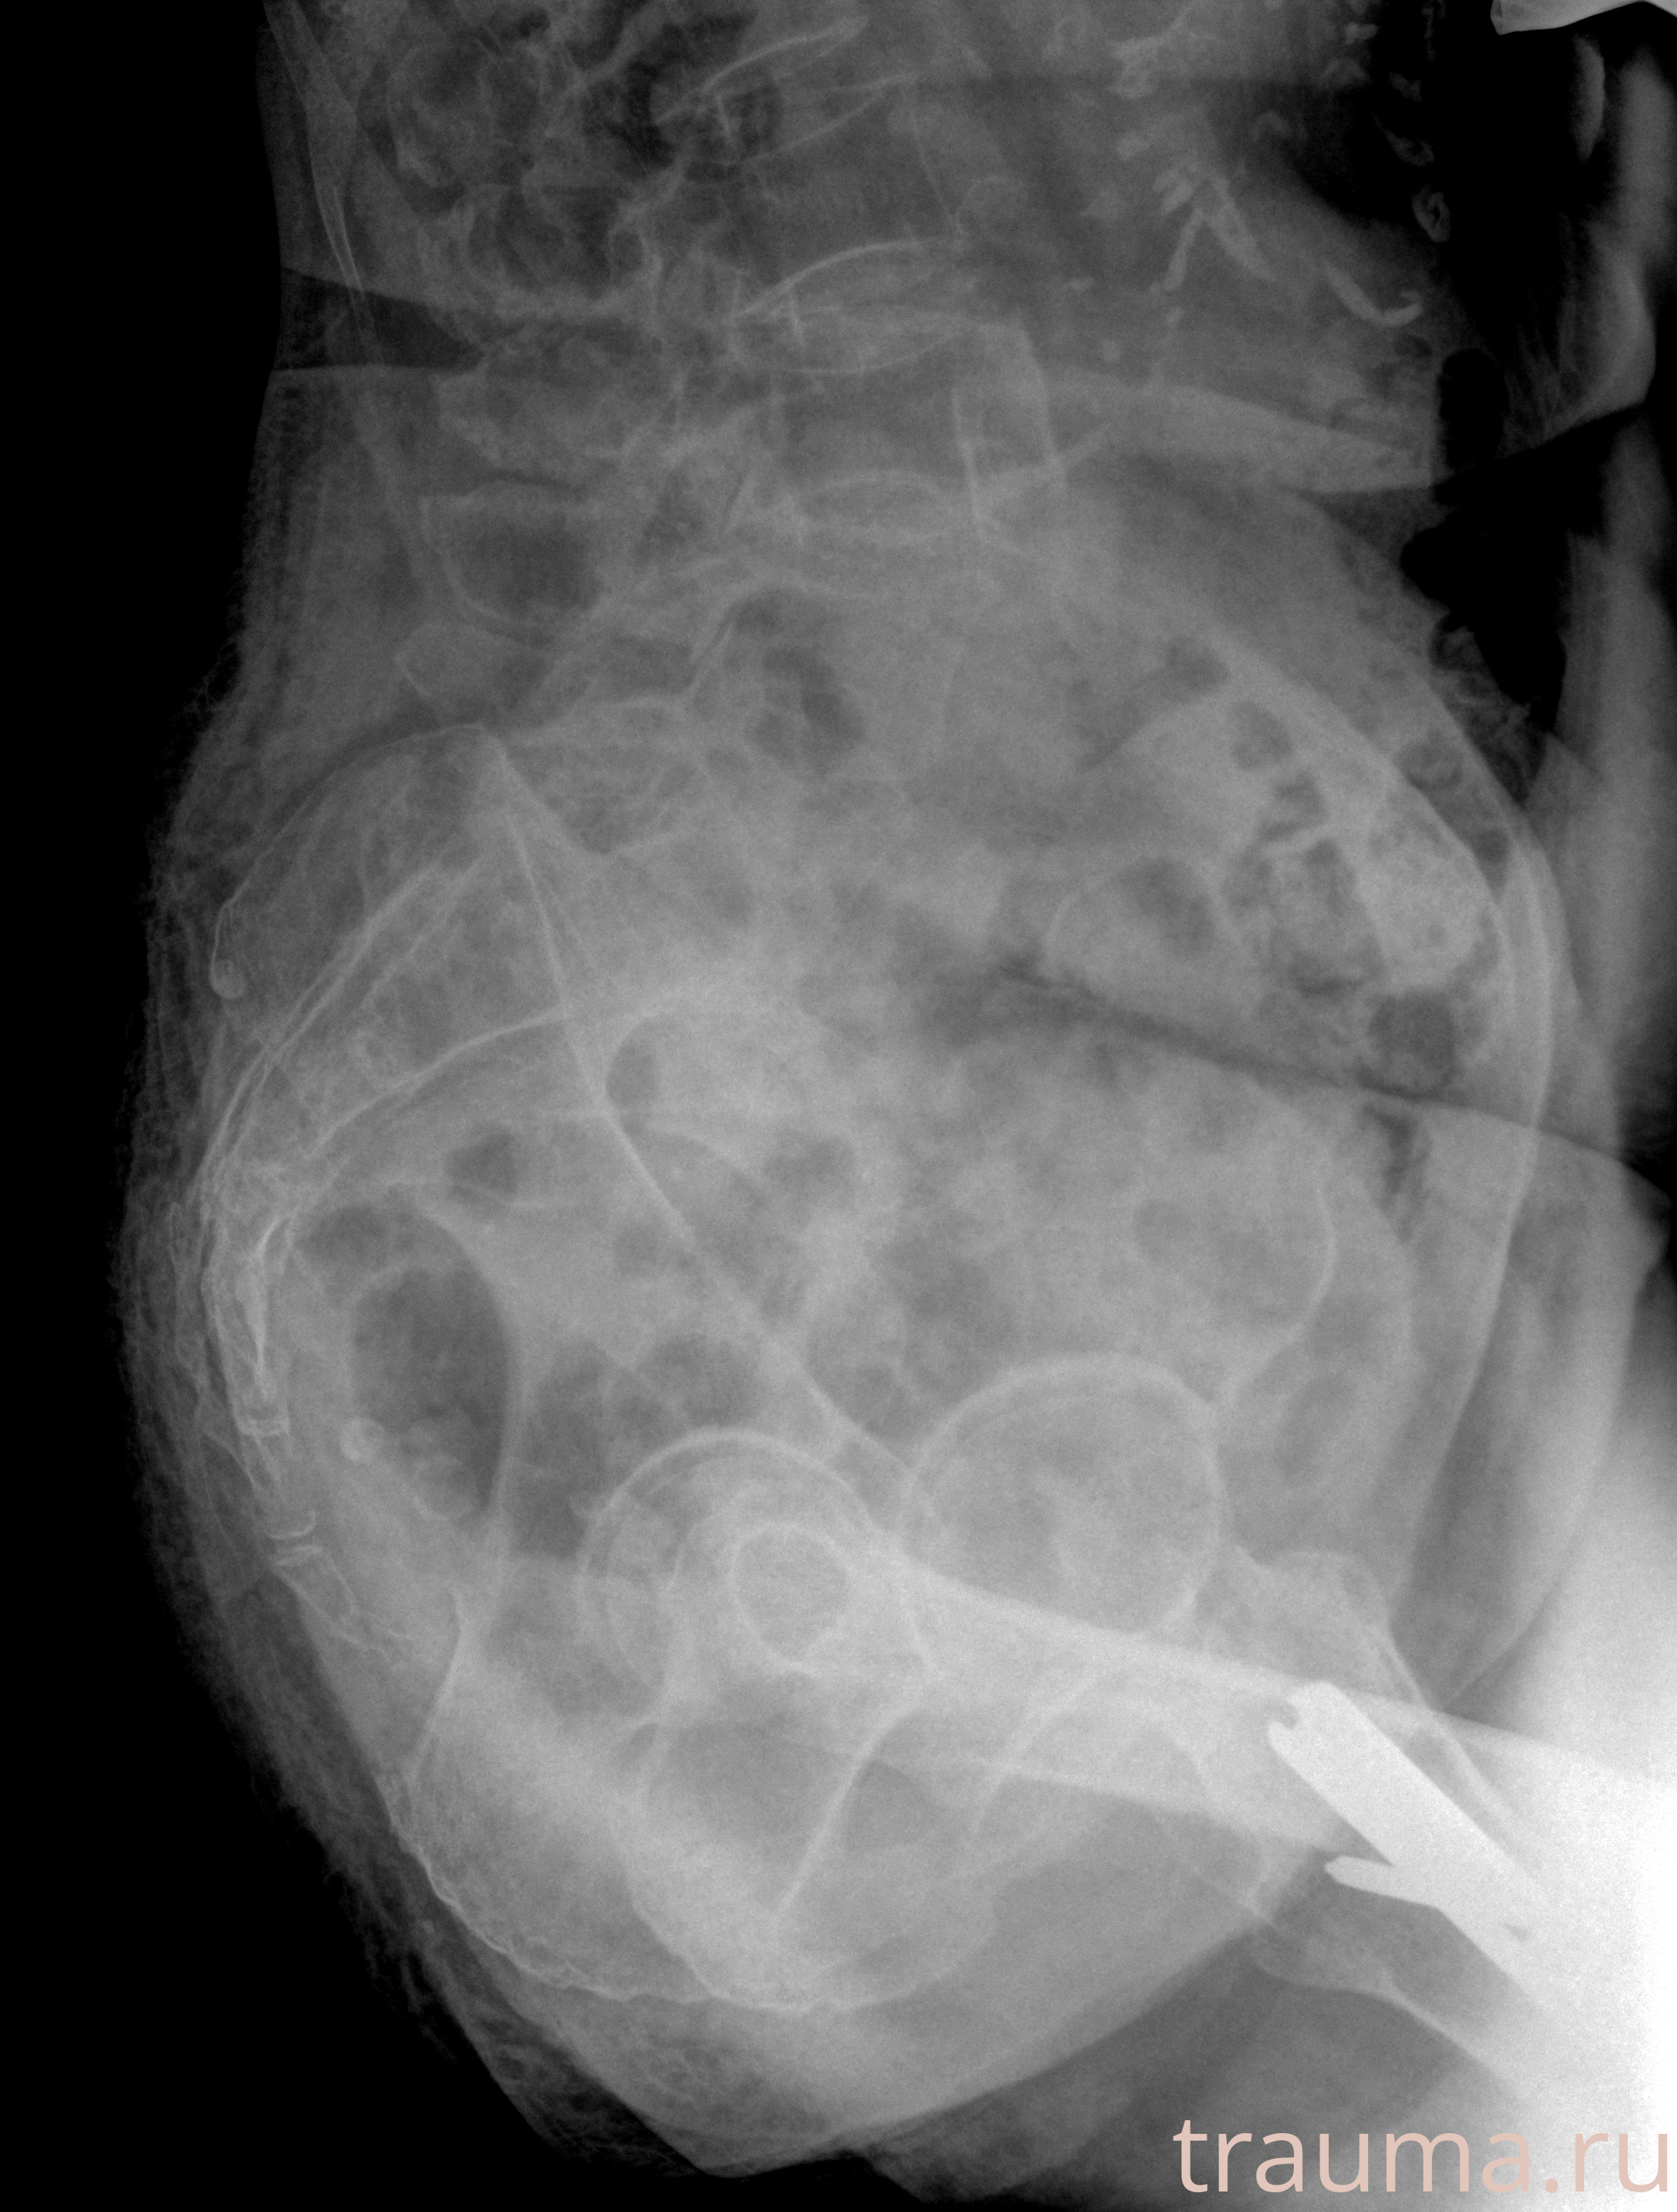

Рентген на дому: по вашему адресу приезжает врач-рентгенолог, травматолог-ортопед с мобильным рентгеновским аппаратом, проводит диагностику травмы или заболевания, делает необходимые рентгенограммы, дает рекомендации по дальнейшему лечению. Получить качественные снимки в домашних условиях возможно благодаря уникальной методике, разработанной МосРентген Центром для института  Склифосовского